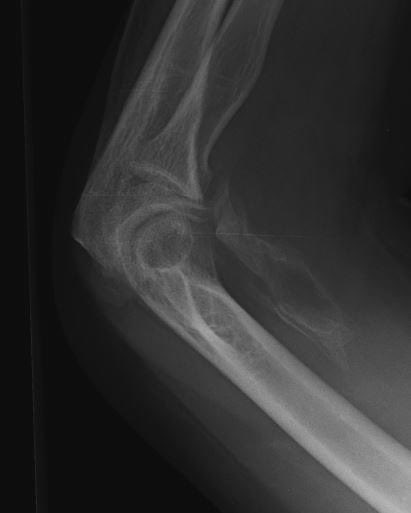

#Case #Radiograph A 25 years old male with of falling down accident of two and half months. Q1) What is your radiographic finding and diagnosis? Q2) What is the management option? #orthopedic 🔹 #MedX #MedEd #MEDHM @IhabFathiSulima